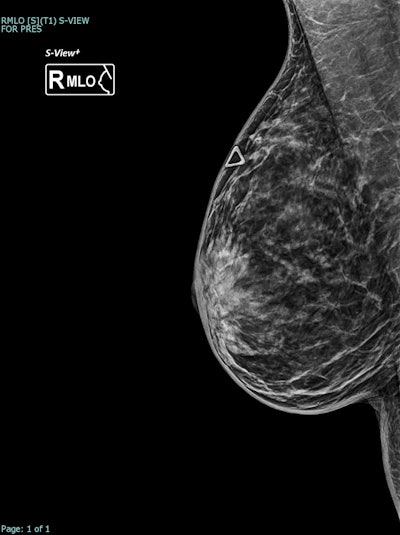

Correlative tomosynthesis, sonographic, and histopathological findings in a 45-year-old woman presenting with a palpable right breast lump. Synthesized 2D mammogram, right breast, mediolateral oblique (MLO) projection. No discrete abnormality is visualized due to extremely dense parenchyma (BI-RADS category D). A retroglandular silicone breast implant is in situ.